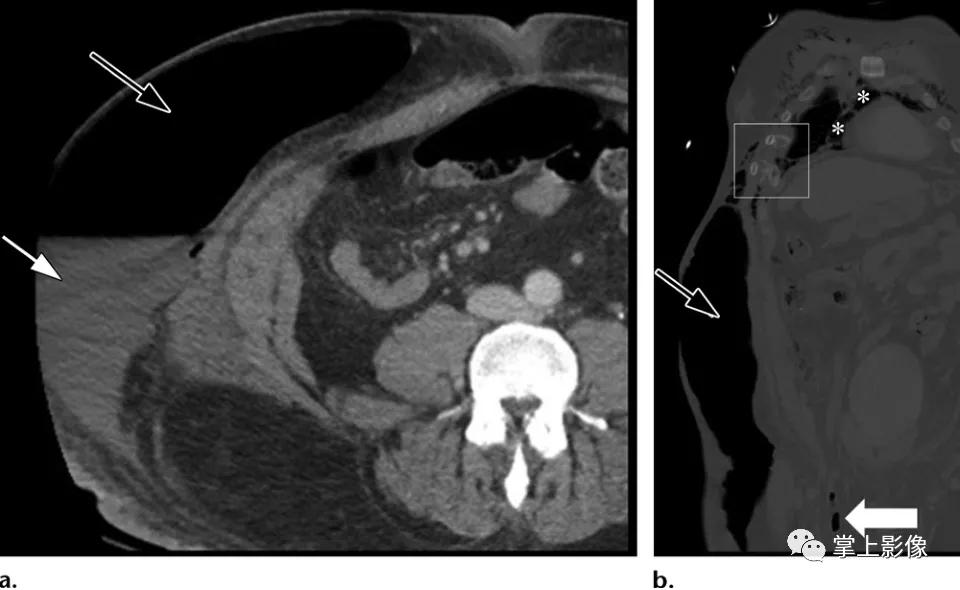

莫雷尔-拉瓦莱损伤(morell-avallee),50岁男性行人,被机动车撞到。轴位(A)和冠状位重建(B)CT图像显示闭合性脱套伤,从右下胸壁延伸至右侧髋部最尾侧,皮下积聚气体(黑色箭头)和液体(白色箭头a)集中在右侧腹壁。冠状重建图像显示了Morel-Lavallee病变的范围和两个移位的前外侧肋骨骨折(b方形轮廓)以及继发于移位的胸骨骨折(未显示)和纵隔气肿(b方形轮廓)。右腹股沟疝显示部分充气小肠环(b中白色箭头)。未见腹内脏器损伤